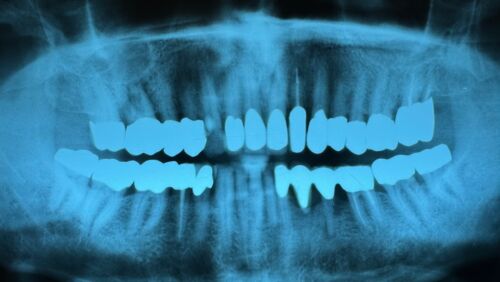

Die Brücke 33 bis 36 entfernt.

Die Zähne 35 und 36 entfernt.

Die Krone 33 abgetrennt und wider hergestellt und am Ende wieder auf den Zahn 33 zementiert.

Die Wunde wurde mit mehreren Nähnmten verschlosse.

Der Patient setzt sein blutverdünnendes Medikament wieder an.

Nun gilt es zu warten, bis die Implantate eingewachsen sind.